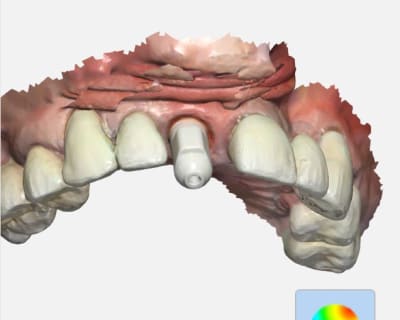

Exemple de ce sue sort une trios 2 de 2013..

Un exemple de scan avec matching emp pour richmond tenon anatomique sous stellite.

> Pas mal pour une vielle dame ! ?

> Les zones proximales entre 6 et 7 ..

Ces images proviennent de quelle camera ?

Trios 2 couleur de 2013...